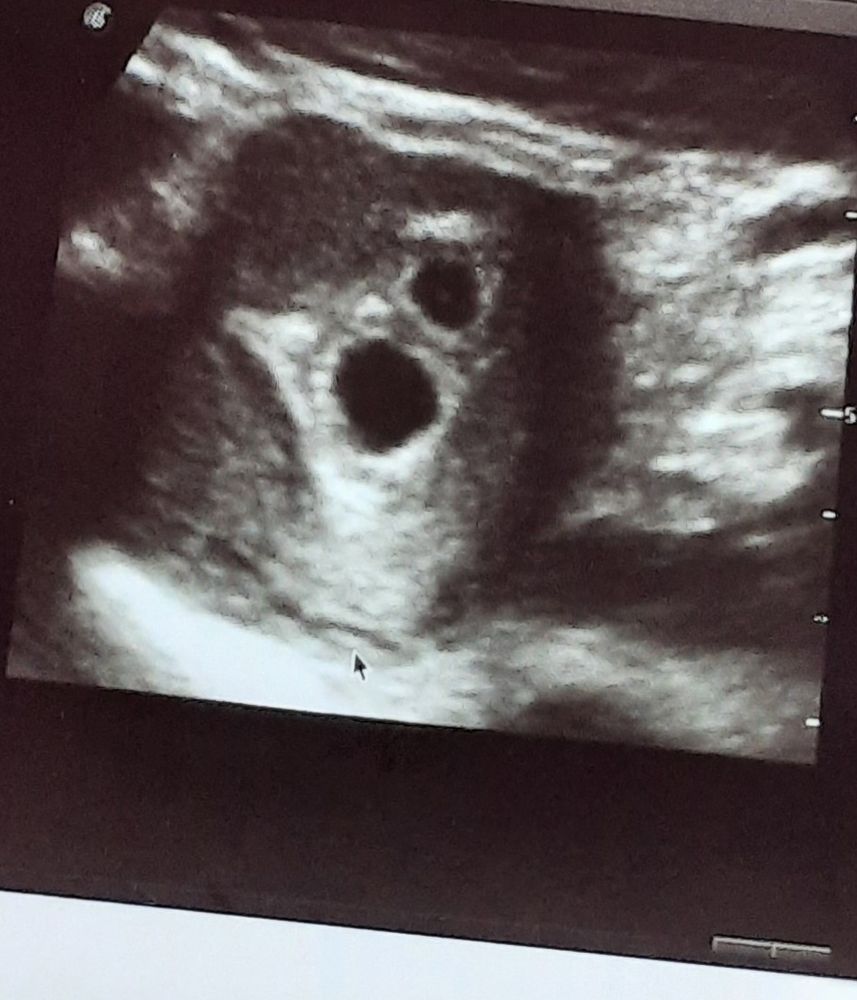

Долгожданное УЗИ

Изображение

Девочки сходила на УЗИ, наконец то, очень надеялась ,что плод в матке, все хорошо, НО, их два, два плодных яйца, я в шоке. Из за стимуляции видимо. Эмбрионов ещё не

Девочки сходила на УЗИ, наконец то, очень надеялась ,что плод в матке, все хорошо, НО, их два, два плодных яйца, я в шоке. Из за стимуляции видимо. Эмбрионов ещё не видно, по эмбриональному сроку 4,5 недели.